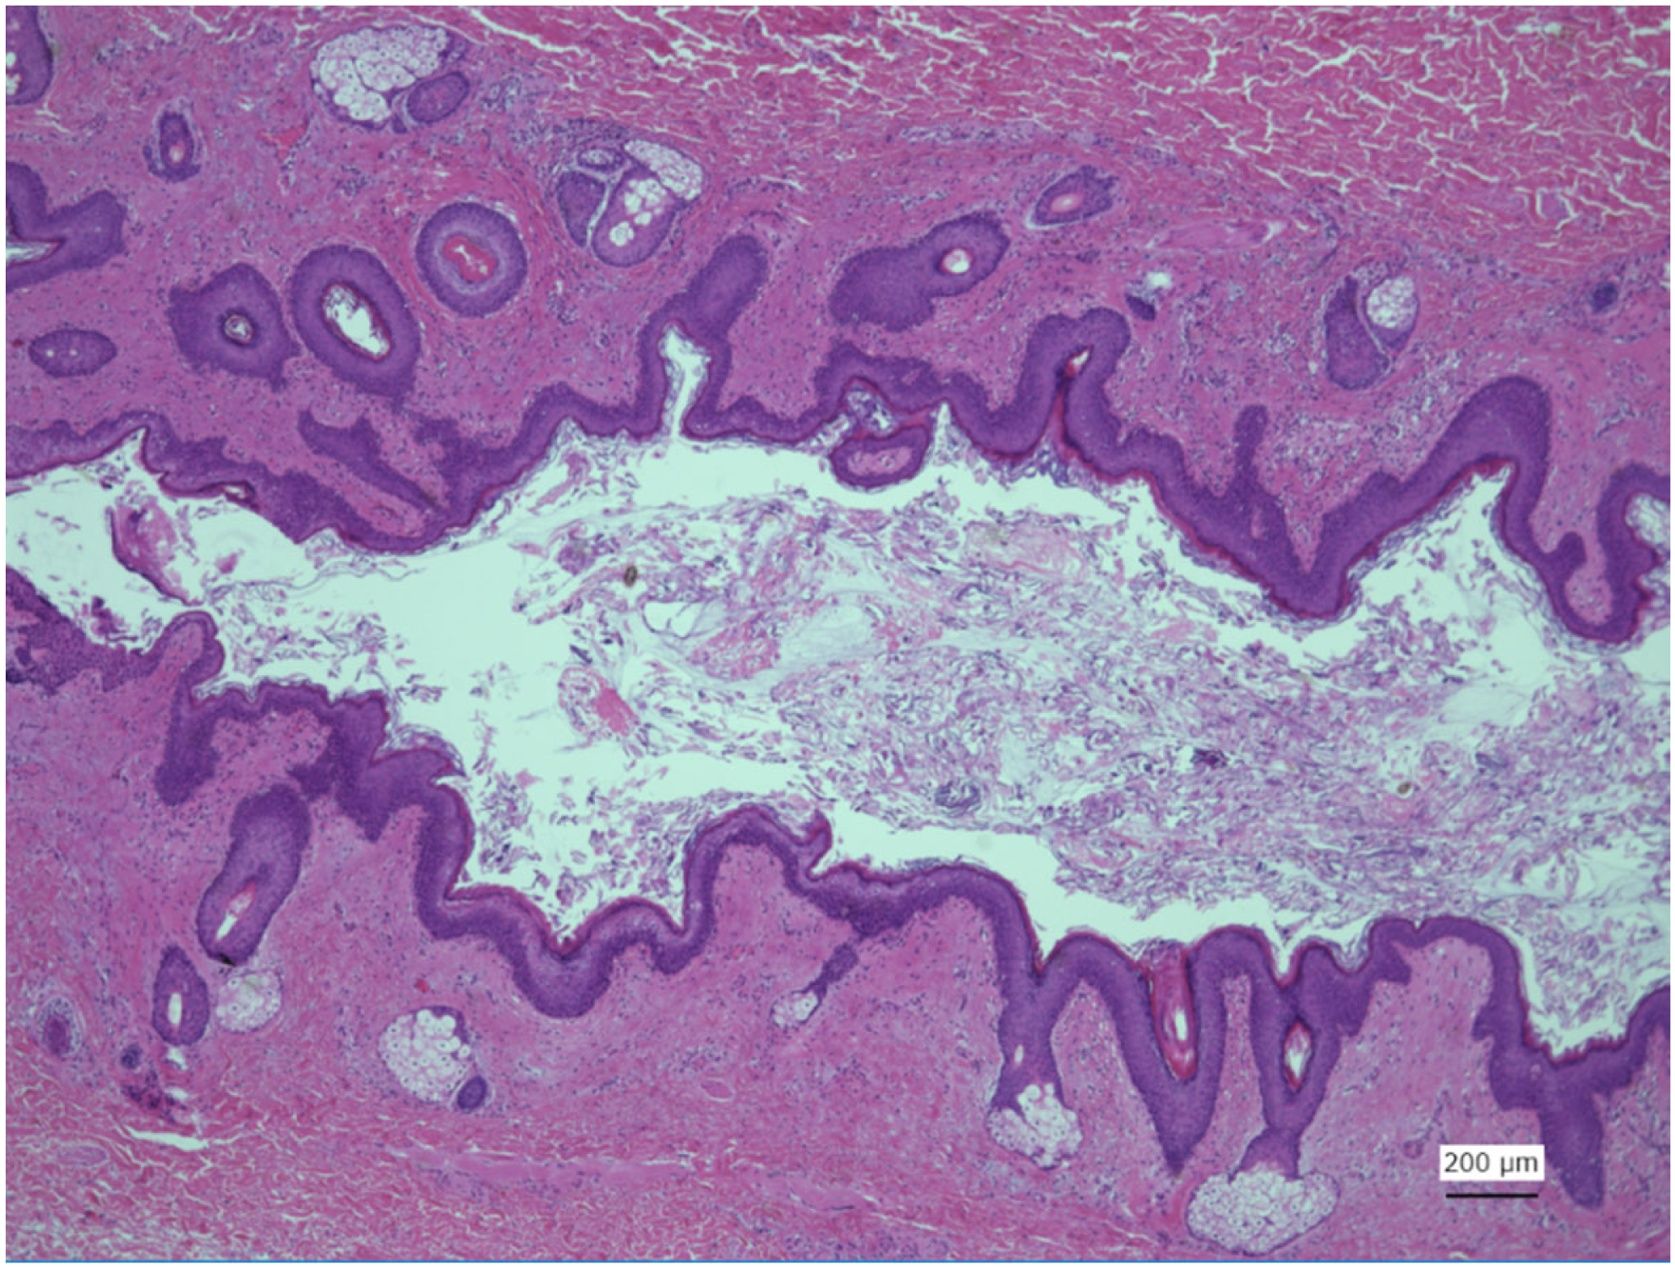

Histological examination of the tract demonstrated that the luminal side was lined with keratinised stratified squamous epithelium with cutaneous adnexal structures such as sweat glands and hair follicles. Salivary glands and ducts were also observed along the duct (Fig. 4).

Micrograph of the section of the tract. The luminal surface is noted to be covered by squamous epithelium. Skin appendage-like structures, including sebaceous glands, sweat glands, and hair follicles, are observed. Salivary gland-like mixed mucous-plasma glands and conduits are also observed in the subepithelial areas.